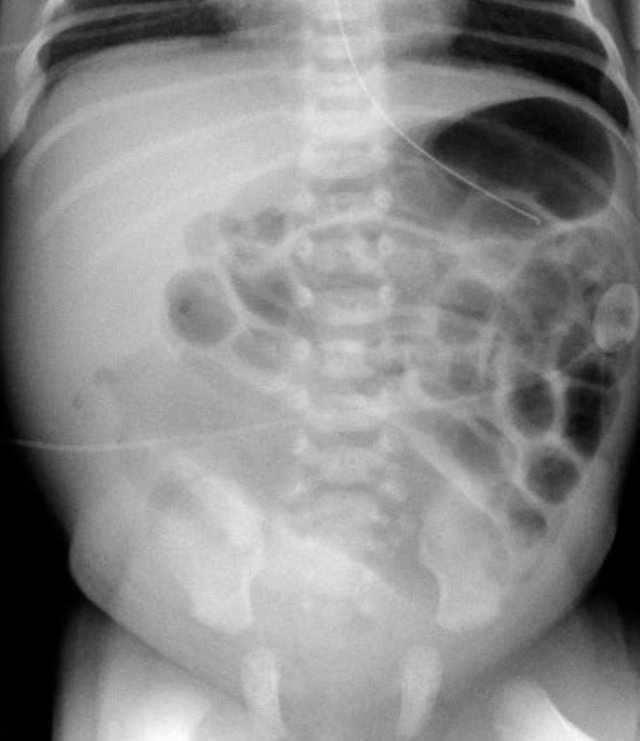

On the left image the bowel is dilated and the diameter exceeds L2 interpedicular width in a patient with meconium ileus.

On the image on the right there is massive dilatation in a neonate with jejunal atresia.

2. Number of dilated loops?

Up til three dilated small bowel loops on an abdominal radiograph generally indicate a high obstruction.

The left image shows a case of jejunal atresia.

More than three dilated loops indicate a low obstruction.

The image on the right is a case of ileal atresia.